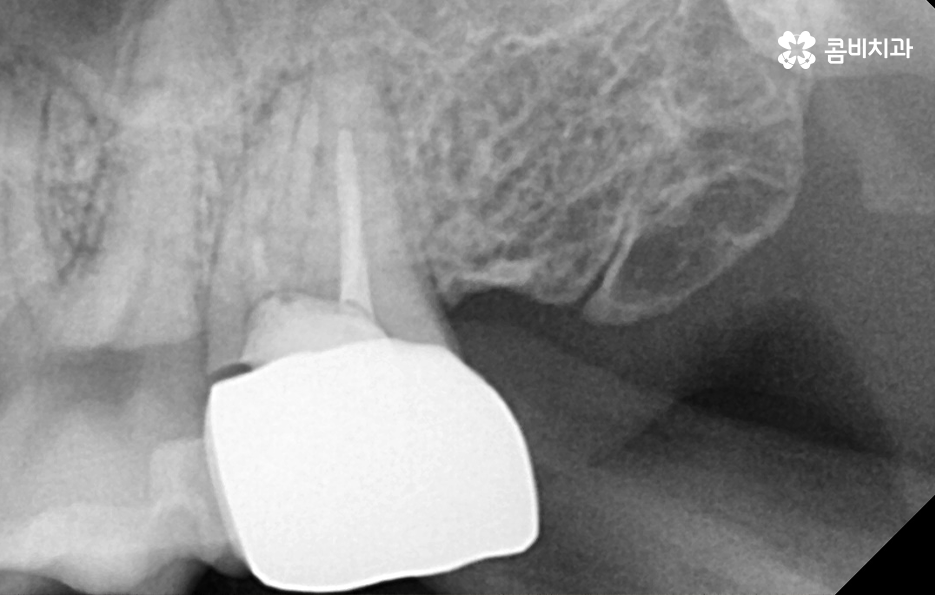

위 치료 사례의 경우 크라운 내부의 2차 충치로 인해 치아 발치를 진행한 사례이기 때문에 치아 상실의 원인이 충치인 경우에는 잇몸 뼈의 상태 자체는 양호한 경우가 많이 있는데요

치아 상실 원인이 발생되고 발치 후 임플란트 치료 계획만 제때 잘 세우신다면 크게 무리 없이 임플란트 치료가 가능한 경우가 많은데 그 이유는 임플란트의 치료 과정에서 중요한 과정이 바로 잇몸 뼈에 임플란트의 인공치근을 식립하는 과정이기 때문이며 임플란트를 식립할 충분한 잇몸 뼈의 두께와 깊이, 골질이 확보되고 전신건강이 양호하다고 가정한다면 대부분의 임플란트 시술은 원활하게 진행될 수 있어요

치아 발치 후에는 보통 약 2,3개월 정도 잇몸과 뼈가 차오르길 기다리며 그 이후에 잇몸 상태가 임플란트를 식립하기에 충분한 상태라면 임플란트를 잇몸 뼈에 식립하고 골유착과정을 약 3개월 정도 거친 후에 지대주를 세우고 보철물을 연결하여 치료를 마무리하고 있어요. 하지만 잇몸뼈 상태가 좋거나, 뼈이식과 동시에 진행하는 경우 발치 후 바로 식립을 진행하는 경우도 있어, 정확한 치료 계획은 의사와 상의를 해보시는 게 좋아요.

임플란트 치료가 끝나면 겉으로 보기에는 자연치아와 거의 유사한 심미성과 적응기간을 거치고 나면 저작력에 있어서 자연치아와 거의 유사한 정도의 저작기능을 수행하고 있는데요

어금니 발치후 임플란트 치료과정은 단계적으로 진행되고 일반적으로 임플란트 구조는 분리형이기 때문에 시술 후 관리 방법에 따라서 보철물의 이상 발생 시에는 사후관리를 통해 해결할 수 있지만 잇몸 뼈에 식립된 인공치근이 염증 등으로 인해 문제가 생기면 심각한 수명 문제로 이어질 수 있기 때문에 사후관리의 중요성이 무척이나 크며 치료만 잘 받는 것이 아니라 오랫동안 꾸준히 사후관리를 믿고 찾을 수 있는 치과를 잘 선택하실 필요가 있어요